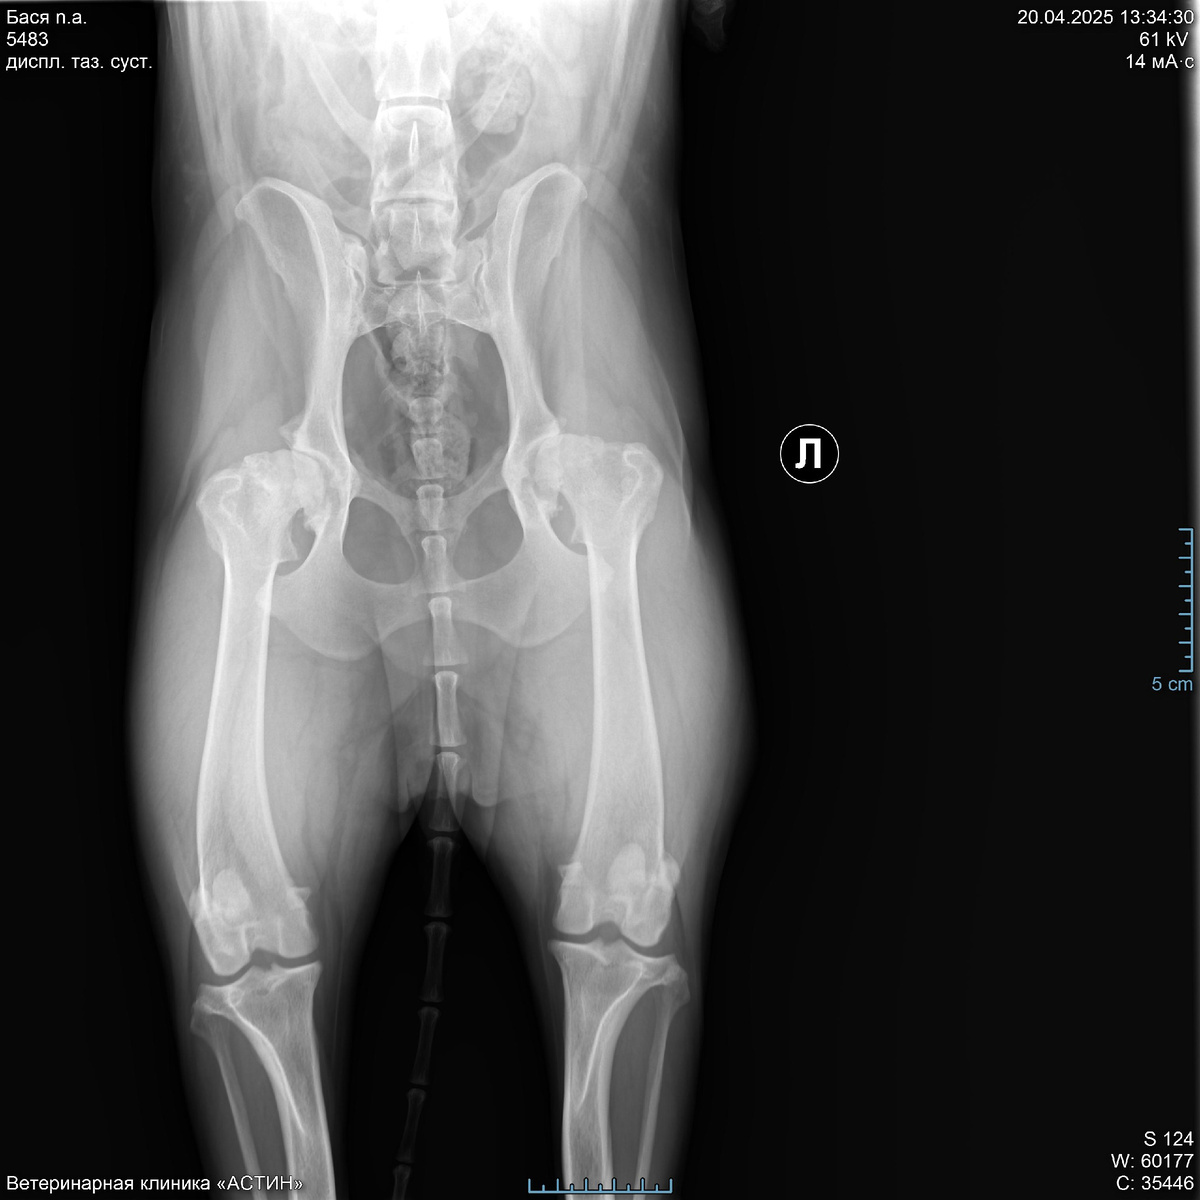

На приеме хирург покрутил и повертел лапы, сделал рентген и сообщил, что ТБС у Баси-то практически и нет. Суставы оба убиты в ноль. Мы, честно говоря, немного обалдели. У нас до Баси был немец и мы знали что такое дисплазия, хотя немец ушел на радугу все же на своих четырех лапах без операций. Но мы думали ,что мы знаем как выглядят больные суставы. Оказалось, что вот эта редкая хромота была вполне себе признаком. Тут мы виноваты, конечно, не досмотрели. Ну и хирургом нам были предложены три тактики дальнейшего лечения. Первая - оставить все как есть. Условно - приложить подорожник в виде все тех же хондропротекторов. Но толку от этого не было бы никакого, так, для собственного успокоения. Вторая - реабилитолог. Походить на плавания, занятия и т.д. Но по честному мнению врача в нашем случае это было бы чуть лучше, чем подорожник. Спасать там было нечего уже. Ну и третий - операция. В этом случае еще 5-6 лет активной жизни у собаки будет. Из минусов - цена. Описав все варианты, доктор отпустил нас, не склоняя и не агитируя ни в какую сторону. За что ему большое спасибо. Конечно, мы были шокированы и испуганы перспективами. Либо обрекать собаку на постоянную боль (а как оказалось, она испытывала постоянную боль уже очень давно) и риск в любой момент получить перелом или травму бедра от любого резкого движения, т.е., фактически, класть собаку спать, или собираться с силами и деньгами и делать операцию. Резюмирую, что решение оперироваться было принято нами с мужем единогласно, т.к. девочку нашу мы любим и хотим ей долгой и счастливой жизни. О нашем решении мы сообщили хирургу и он рекомендовал нам клиники, которые делают подобные операции в Москве. По сути, их всего две.